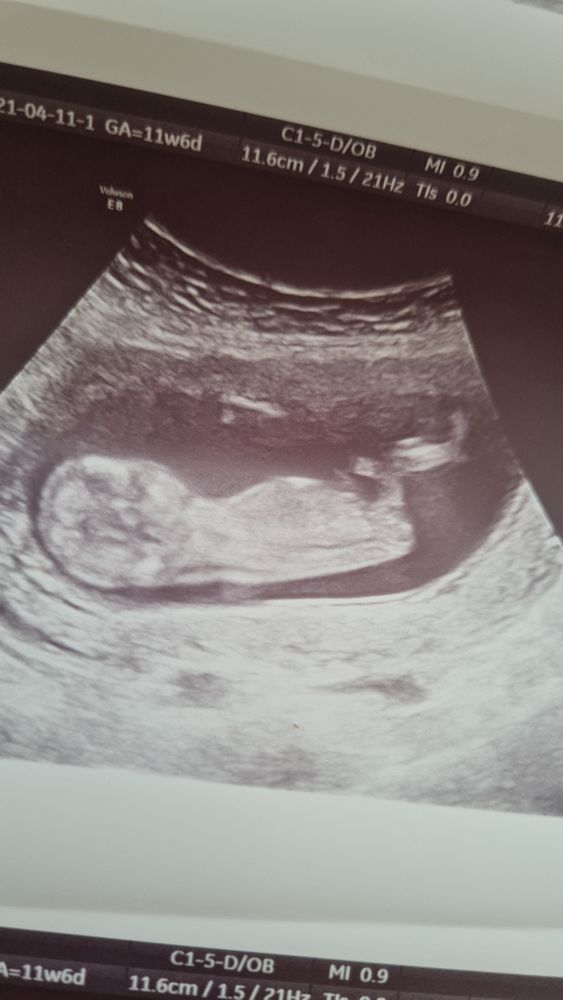

Узи 12 недель

Срок ровно 12 нед,по узи 12.4...КТР 61см, сердцебиение 165

На первом фото непонятно то-ли бугорок то-ли пуповина... Врач сказала непонятно совсем,может больше и к мальчику) так долго ждать ещё до 20 нед)))